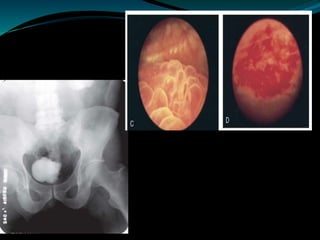

 The cystogram films may show a small contracted

bladder due to excessive fibrosis (thimble bladder).

 Thimble or systolic bladder – inability to relax and

distend (capacity <100ml)

IVU of ureter and bladder

Cystoscopy and Ureteroscopy

 Endoscopy plays a limited role in the diagnosis of TB.

Despite direct visualization of lesions, there are no

pathognomonic findings that are specific for

tuberculosis.

 Ulcerative lesions may mimic malignancy. A “golf-

hole” ureteric orifice is suggestive of tuberculosis, and,

when found, upper tract imaging or endoscopy should

be obtained .

 However, a biopsy should be done when in doubt of

malignancy.